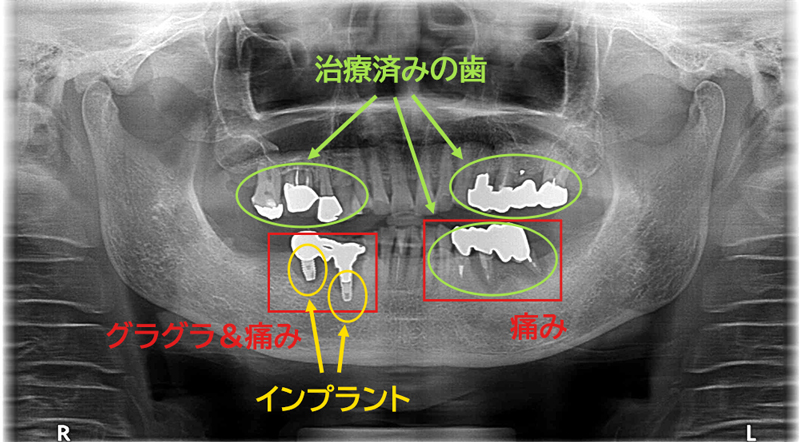

他医院でインプラント治療を行ったが、治療後に「インプラントがグラグラする。」「インプラントが痛い。」などの症状を発症。「インプラントは問題なく埋まっている。咬合調整をすれば症状は改善する。」と言われ、数か月間通院したが一向に改善しなかった。そこで、クリニック長が日本口腔インプラント学会専門医である当院にセカンドオピニオンで来院。

こちらは、先述のセカンドオピニオン来院時のレントゲン写真を拡大した写真です。

インプラントの周りが、少し色が変わっています。骨吸収が起きてしまっています。これは骨が溶けてなくなってしまっている状態です。

インプラントを支えている骨が無くなってしまっているので、インプラントがグラグラしてしまいます。このまま放置すると、更に骨が無くなっていき、ついにインプラントが抜け落ちてしまうことが予想されます。